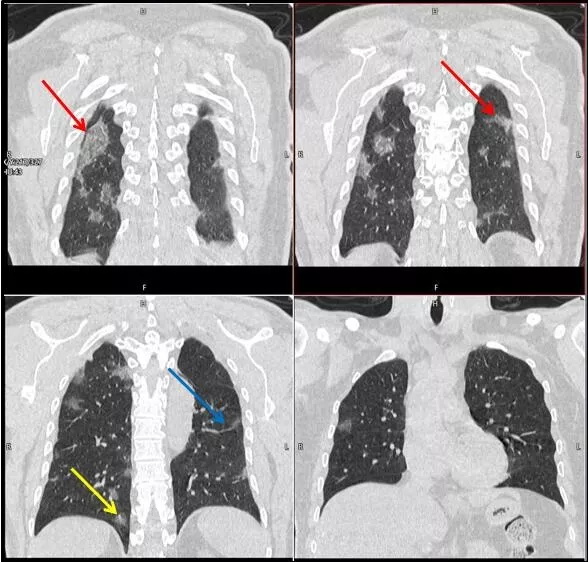

武漢大學中南醫(yī)院影像科副主任張笑春教授發(fā)現,目前武漢市家庭聚集性發(fā)病較多,而且大多起病隱匿,一次甚至多次核酸陰性,無任何臨床癥狀,CT檢查卻已顯示為病毒性肺炎特征。

為了盡快篩查新型冠狀病毒肺炎患者,醫(yī)院會選擇影像診斷作為早期發(fā)現新型冠狀病毒感染的肺炎的重要一環(huán)。

CT為當前首選篩查與診斷的主要影像學手段,胸部CT的病毒性肺炎檢出率高。